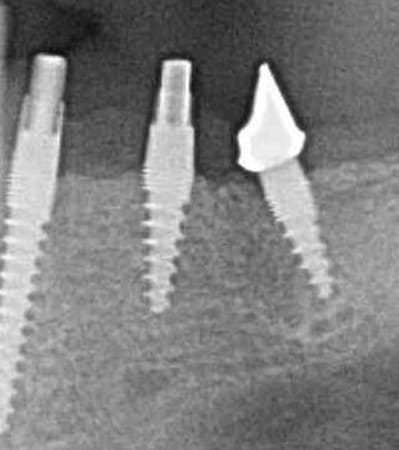

> le pilier distaL, EST-CE DE LA ZIRCONE SUR LE PILIER CIMENTÉ?

Oui,c´est un Prep cap zircone , que je cémente juste après l´implantation immédiate pour mieux former la gencive. Les implants monoblocs ont étés implantés entre 40 et 60 Ncm . Les photos 6 et 8 on voit les prep cap juste après l´implantation immédiate ce sont des sortes de "couronnes" pré fabriquées.

L'axe de la 45 me semble pas très conventionnel...

Merci

Bonjour Ceramik,

Oui , tu as raison pour la 45, en fait quand j´ai enlevé la 45 j´ai choisi l´axe comme ca ( dans l´os dur et en bon santé) parce que c´etait ici que je pouvais avoir la stabilité ( pour cet implant à 50 Ncm.

Oui les prep caps c´est possible de le faire en bouche , ou alors si il y a la forme qu´il faut au départ on les cémente juste (il y a une photo) , et le cement ne va pas en dessous du prep cap .

Avec des bons forets et de l´eau ( des diamants on dit je crois) c´est très facile à preparer. Avec une bonne aspiration les petits bouts partent .

Voilà une patiente que je revois à deux ans apres la pose d'un monobloc Classic line 3,5/12mm et prep cap zircone 12 degres 2/2 en 24.

La dent 25 était une couronne massive (dent à tenon type richmond) que j'ai taillé en inlay core.

Pour répondre à Céramik, oui la zircone se taille en bouche ( fraise Komet spécifique recommandées verte et blanche..mais tout diamant fait l'affaire). A la pose des céramo metalliques on observe la prep cap zircone au niveau du joint de

la couronne.

Radios 1,2,3 photo 1= jour de la pose de l'implant.

radio 4 photo 2 et 3= 8 semaines post pose de l'implant, ceramiques scéllées.

Radio 6, photo 4 et 5 controle à 24 mois.

Deux ans plus tard, la gencive a recouvert la zircone et on observe à la radio un gain osseux au niveau des micros spires.